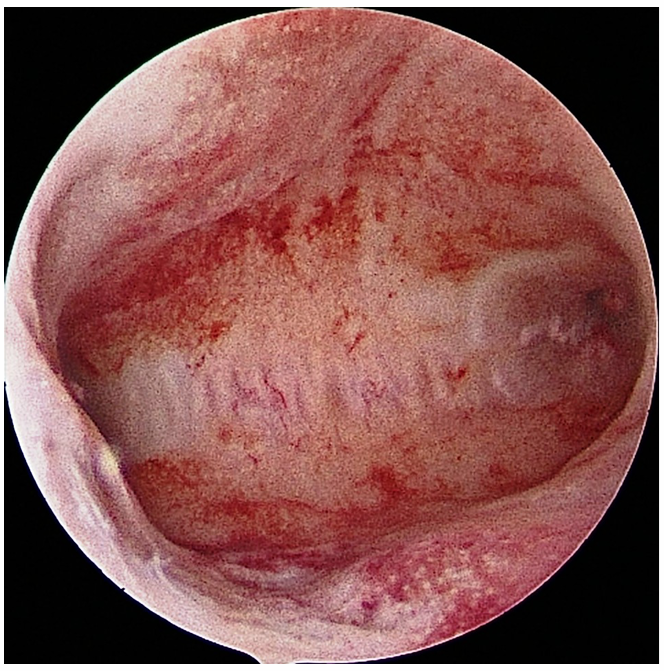

3. The hysteroscope is gently guided into the uterus.

4. We release a fluid (usually saline) to expand the uterus, giving us a clear view of the lining and the openings of the fallopian tubes.

5. If we find issues like polyps or adhesions, we can remove them using tiny instruments.

The procedure is usually quick, often taking less than 30 minutes.